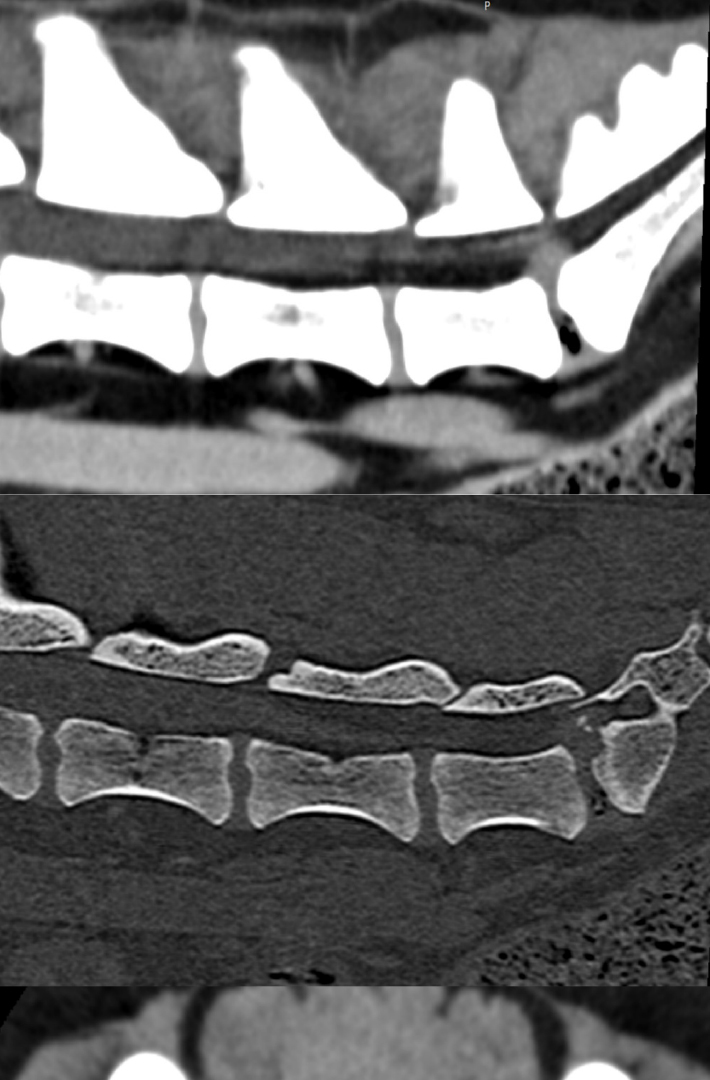

Wenn ein Hund typische chronische Symptome zeigt, kann man den Verdacht auf eine lumbosakrale Stenose äußern. Neben der allgemeinen Untersuchung ist eine entsprechende orthopädische und neurologische Untersuchung wichtig. Typisch sind dabei ein Druckschmerz in der hinteren Lendenwirbelsäule, Schmerzen bei der Hüftstreckung, eine Muskelatrophie im unteren Rücken oder in den Hinterbeinen. Neurologisch ist ein propriozeptives Defizit häufig, also ein Sensibilitätsverlust an der Hinterextremität. Außerdem kann der Flexorreflex vermindert sein, und eine Besonderheit ist, dass gleichzeitig der Patellarreflex gesteigert ist. Man spricht dann von einer Pseudohyperreflexie. Die weitere Diagnosefindung erfolgt mittels bildgebender Verfahren. Breit zugänglich ist das Röntgen – dabei können degenerative Veränderungen am lumbosakralen Übergang dargestellt werden. Das Ergebnis hängt jedoch stark von der Aufnahmetechnik sowie der Lagerung des Patienten ab; nicht alle Pathologien sind dabei ersichtlich. Weiters entspricht ein Röntgenbild alleine nicht dem Schmerzempfinden des Tiers. Mithilfe eines Röntgenbilds kann man jedoch etwaige Differenzialdiagnosen wie eine Hüftgelenksdysplasie ausschließen. Sofern von der Klinik oder im Röntgenbild eine Problematik im Wirbelkanal vermutet wird, ist ein CT oder MRT zu empfehlen. Erst so kann man die diversen Veränderungen definitiv feststellen und eine entsprechende Therapie planen. Anders ausgedrückt: Ein Röntgenbild lässt vermuten, ein Schnittbildverfahren gibt Sicherheit. CT und MRT sind übrigens laut einer Studie bei pathologischen Befunden im Bereich des lumbosakralen Übergangs ziemlich übereinstimmend.